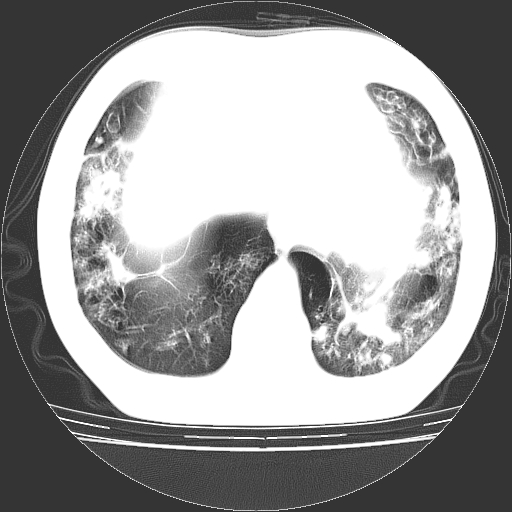

以下是引用zyx168在2006-12-4 15:30:00的发言:[br]经典!支气管肺囊肿并感染。

以下是引用dyqct在2006-12-4 17:11:00的发言:[br]典型的囊状支扩合并感染。

以下是引用liaoqiang在2006-12-4 16:12:00的发言:[br]局部肺叶内可见扩张的支气管壁,考虑为支扩。部份囊样影内有小液平和肺内散布斑片征影、小结节及纤维灶,提示支扩伴感染,且由于局部呈现有树芽征感染以结核可能性大。

以下是引用zhoucan076在2006-12-4 16:48:00的发言:[br]囊状支扩合并感染